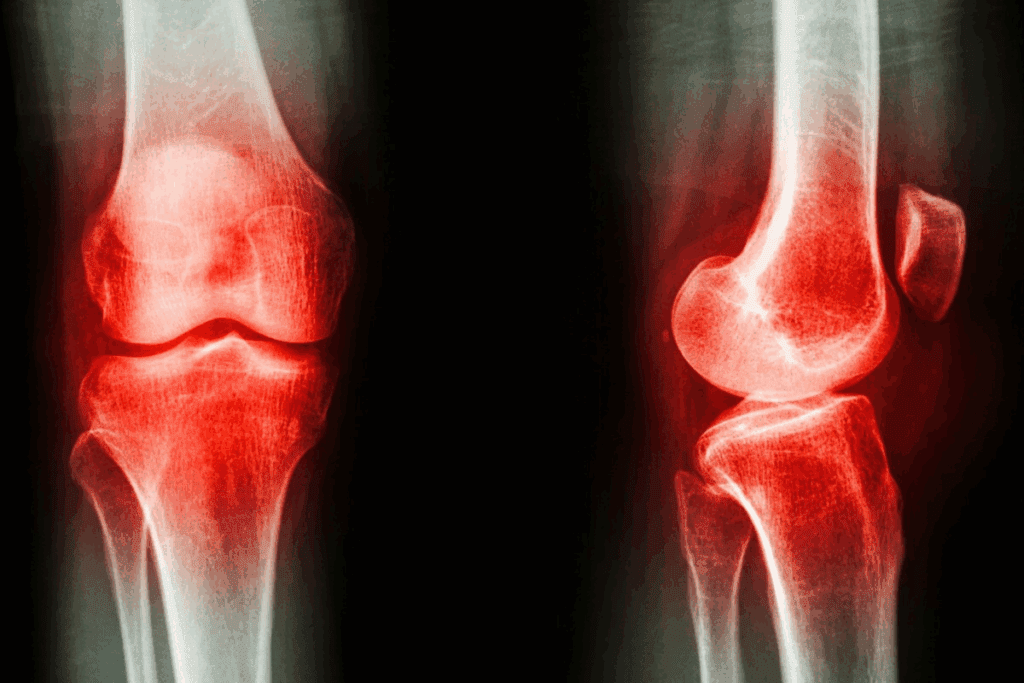

Understanding Osteoporosis and Its Impact on Bone Health

Osteoporosis weakens bones, posing a big risk to health, mainly for older adults. It causes bones to lose density and quality. This makes bones more likely to break.

What Is Osteoporosis and Who Is at Risk?

Osteoporosis is called a “silent disease” because it often goes unnoticed until a bone breaks. Many things can raise your risk, like age, gender, and lifestyle. Women, after menopause, are more at risk because of lower estrogen levels.

Key risk factors include family history, low BMI, and certain medicines like corticosteroids. A diet lacking in calcium and vitamin D, smoking, and not being active also increase risk.